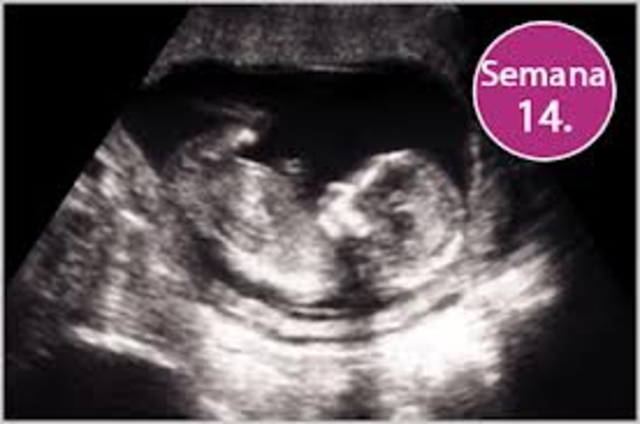

• (14 semanas):

(14 semanas):

En la semana 14 se aprecia su aspecto humano las orejas están en su lugar definitivo y los delgados parpados se mantendrán cerrados hasta el séptimo mes